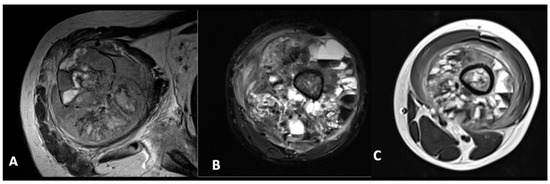

2.2. Analysis and Definition of Study Variable